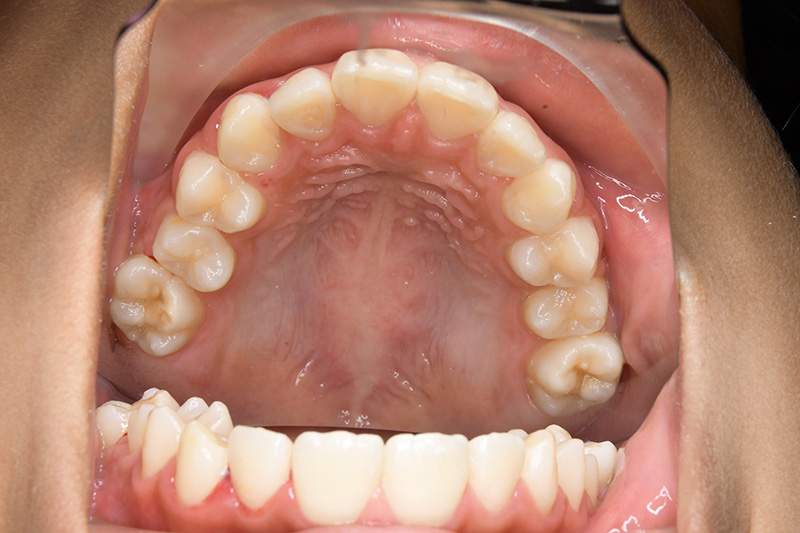

| 顔貌所見 | 正貌はほぼ左右対称。側貌はstraight type、引き締まった口唇形態をしていた。 |

| 口腔内所見 | over jet 2.5mm、over bite 2.0mm、右側大臼歯関係はEnd on class Ⅱ、上顎左側Eは早期喪失により左側大臼歯関係はFull classⅡ、右側Eは6の異所萌出により歯根吸収が進行したため一般歯科医院にて抜去済みであった。 |